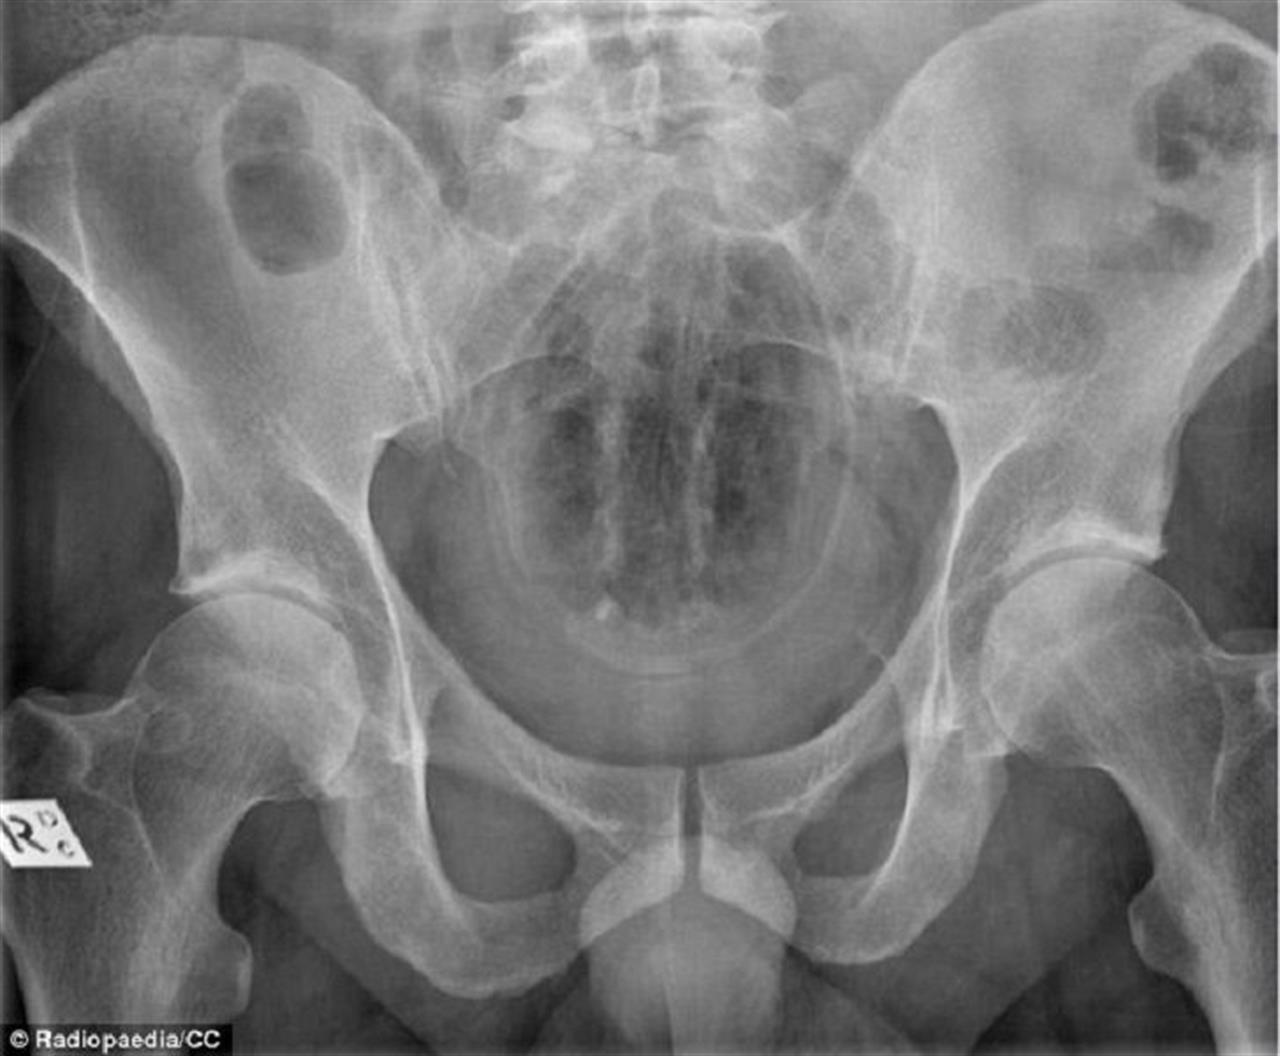

▼美國消費者產品安全委員會(CPSC)發布了2018年急診室就診的數據檔案,發現急診室的醫生不斷的從人類的直腸、下體、喉嚨、耳朵甚至鼻孔取出各種各樣的物品,這些物品的種類包羅萬有,許多甚至會令人感到不可思議!就好像這個案例中,患者直腸中竟然有個咖啡罐!